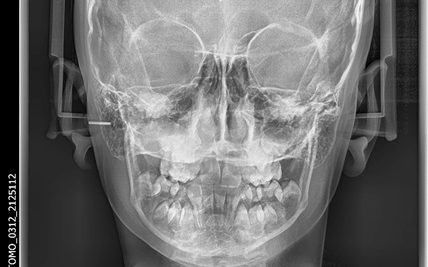

Asymmetry of the head structures is evaluated. Upper jaw, lower jaw, nose, eye sockets, mandibular ramus is used to assess whether or not asymmetric. In orthognathic surgery patients, whether the structures are asymmetric or not is evaluated.